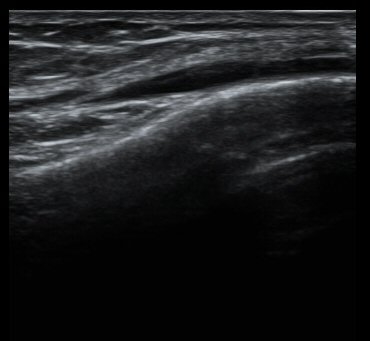

¹«¸­ ³»ÃøºÎÀδë Á¾´Ü¸é°Ë»ç¿¡¼­ ³»ÃøºÎÀδë Ç¥Ãþ±ÙÀ§ºÎ Àú¿¡ÄÚ ºÎÁ¾ ¹× ½ÉÃþ±ÙÀ§ºÎ ºÎºÐÆÄ¿­ÀÌ

°üÂûµÊ(±×¸² 3, 4).

¹«¸­ µÚ¿¡¼­ °üÂûÇÑ ÈĹæ½ÊÀÚÀÎ´ë °æ°ñºÎÂøºÎ¿¡¼­ ƯÀÌ ¼Ò°ßÀ» º¸ÀÌÁö ¾ÊÀ½(±×¸² 5).